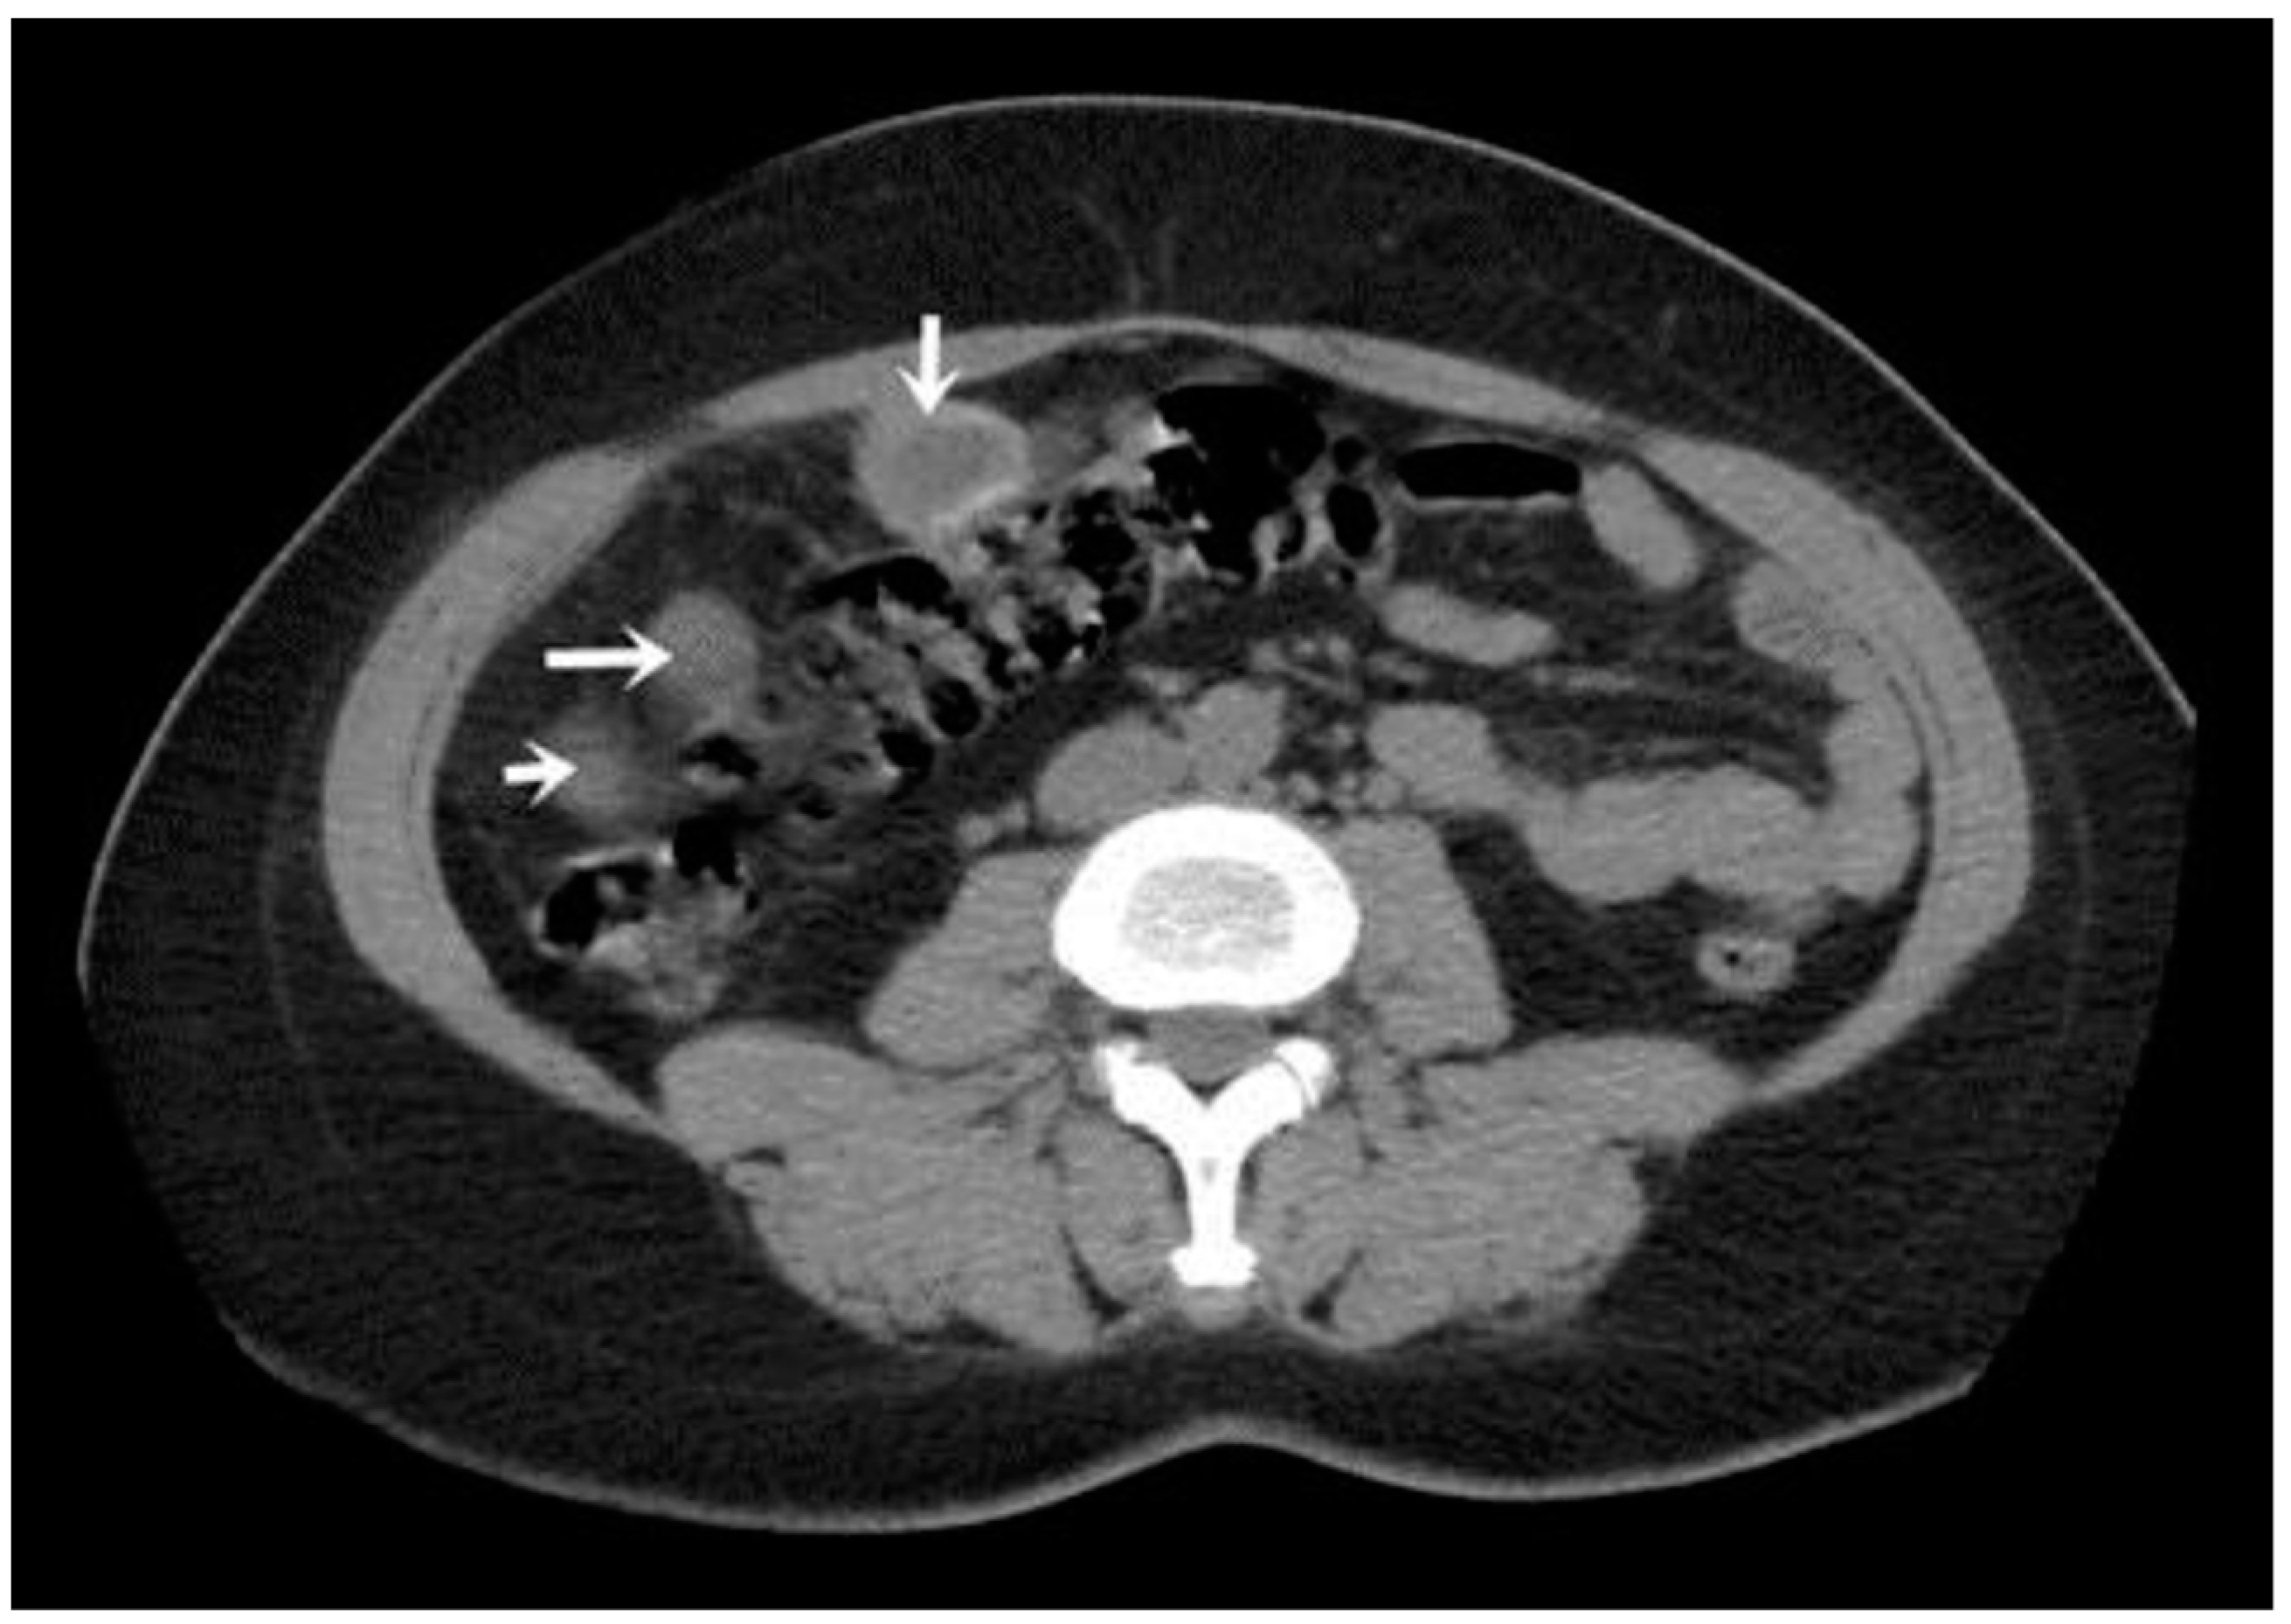

A CT examination revealed multiple cystic images in the hepatic segments V, VI, and VII, with subhepatic extension and involvement at the fissures of the venous ligament. Cystic images were also observed in the anterior abdominal wall and submesocolic (Figure 5, Figure 6, Figure 7, Figure 8 and Figure 9). Blood tests showed no significant abnormalities, and ELISA determination of IgG class antibodies to Echinococcus granulosus was positive at 1.66 IV (with values considered negative at ≤0.9 IV and positive at ≥1.1 IV).

The imaging highlights hepatic cysts in segments V, VI, and VII, a large cystic formation in the round ligament, a cyst in the parietal peritoneum, two cysts in the greater omentum, and two cysts located in the submesocolic enteral mesentery.

Figure 4. Peritoneal and segment V cyst (indicated by arrows).

Figure 5. Omental hydatid cysts (indicated by arrows).